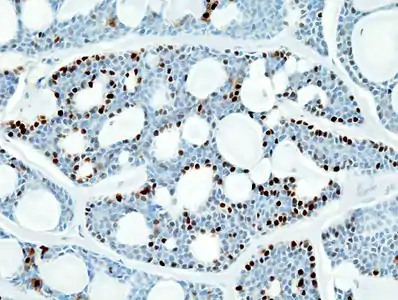

- Histopathological image of adenoid cystic carcinoma of the salivary gland, immunostain for S-100 protein